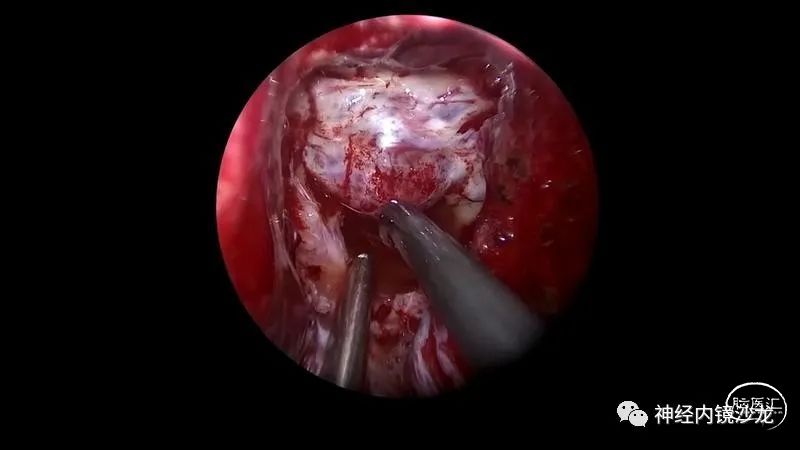

精彩图表

从事神经外科十余年,擅长神经外科肿瘤诊治,尤其是神经内镜微创手术治疗垂体瘤、颅咽管瘤、脑膜瘤等颅底肿瘤